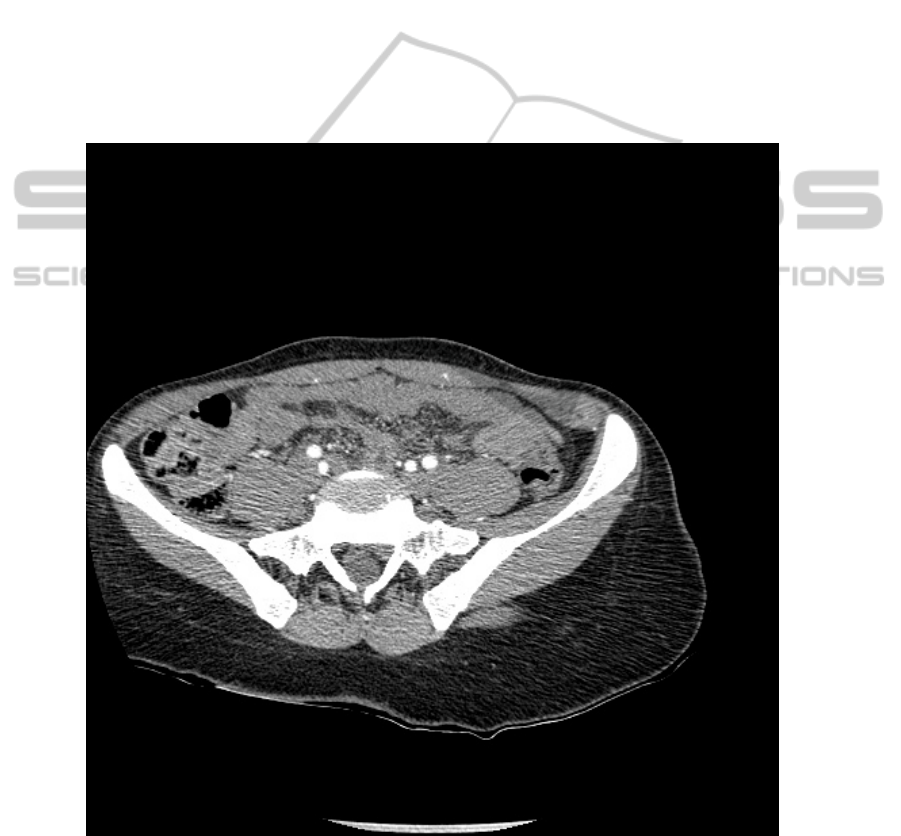

18. Manesh Kokare, CT Image Retrieval Using Tree Structured Cosine Modulated Wavelet

Transform, International Conference on Digital Image Processing, 2009.